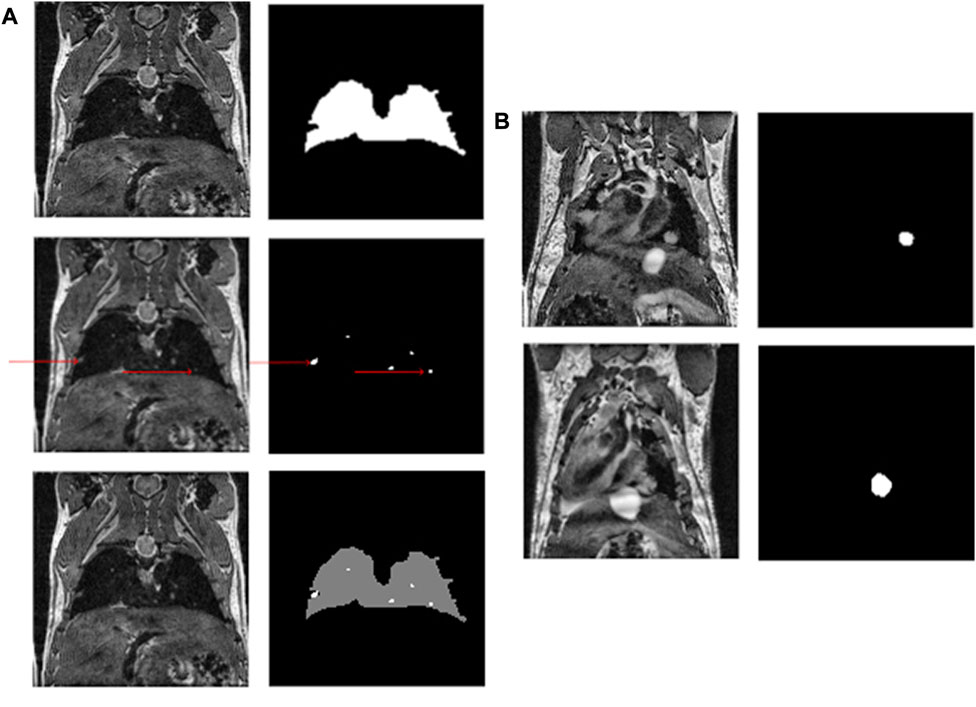

2.10 Post-processing pipeline

FIGURE 2

www.frontiersin.org

FIGURE 2. (A) An example of a mouse slice, the lung and metastasis masks (red arrows indicate metastases) and the multiclass resulting mask. (B) Shows the growth of a metastasis over time.